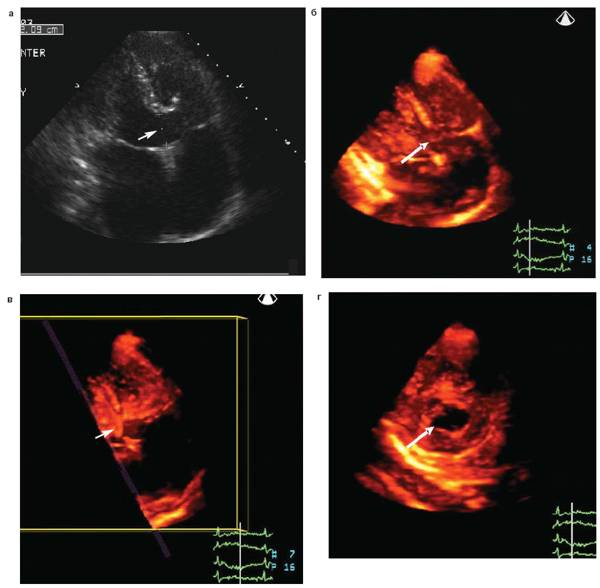

Стрелка указывает на вторичный дефект межпредсердной перегородки.

Гемодинамика. Суть гемодинамических нарушений это артерио-венозный сброс из левого предсердия в правое, что приводит к гиперволемии малого круга кровообращения, диастолической перегрузке и дилатации полости правого желудочка. Величина сброса может достигать 10-15 л/мин. Возникает перегрузка ПЖ, его дилатация, переполнение кровью легочных сосудов, легочная гипертензия, которая вначале носит рефлекторный характер из-за спазма артерий ведущая к постепенной облитерации. Склеротическая фаза наступает после 25-30 лет.